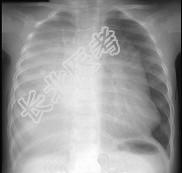

- 单项选择题12岁,女, 咳嗽、咯血1个月,咳出毛发、钙化物, 请结合图片,选择最可能的诊断 ( )

D、畸胎瘤